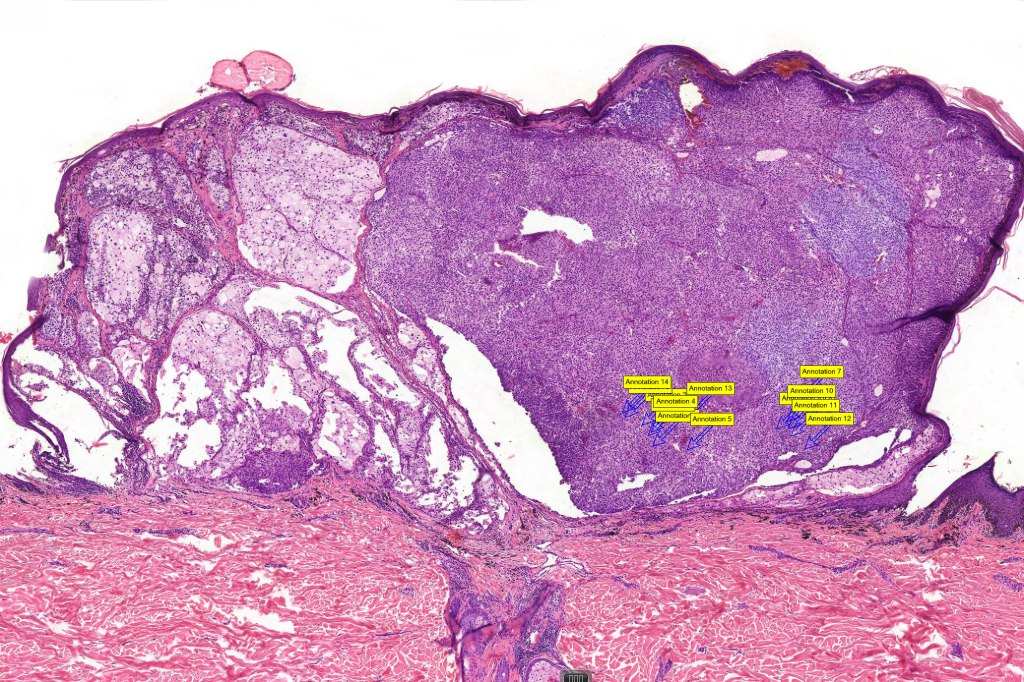

•Very rare variant of melanoma

•Back> lower & upper extremities> head & neck> choroid

•Often ulcerated nodules

•Poor prognosis is likely related to large tumor size at presentation

•May affect the tumor in part or whole

•Enlarged cells with copious eosinophilic, foamy or clear cytoplasm (some authors include melanoma with clear cell change in the same category)

•Variable pigmentation